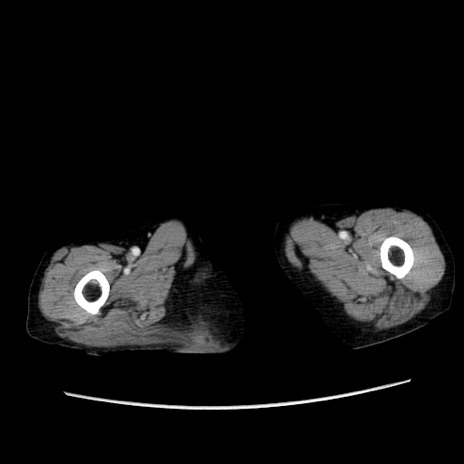

症例25(横断像)

【症例】80歳代女性

【主訴】胸のつかえ感

【現病歴】約9時間前に食後から胸のつかえた感じあり、嘔吐あり、来院。

【既往歴】胃癌(全摘)、胆摘、虫垂炎

【身体所見】心窩部に圧痛あり、反跳痛なし。

【データ】WBC 5700、CRP 0.05